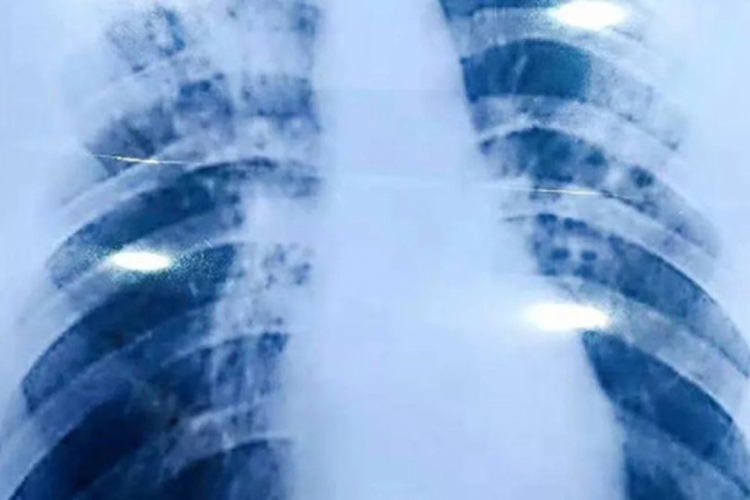

A tuberculose é uma doença infecciosa e transmissível que afeta principalmente os pulmões. Ela é considerada pelo Ministério da Saúde como um “sério problema de saúde pública, com raízes sociais”.